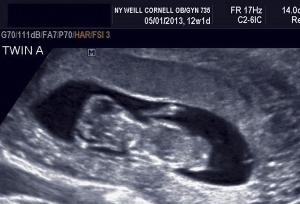

Early imaging is key to the diagnosis of the many anomalies that are unique to multifetal gestations. The third slideshow of our ultrasound collection includes examples of these anomalies.

Ultrasound imaging is a key prenatal tool for revealing structural anomalies that may point to genetic conditions. This slideshow is Part 1 of our collection of ultrasound anomalies and includes first-trimester anomalies and second-trimester anomalies of the head and brain. Part 2 will discuss second-trimester anomalies of the body and limbs.